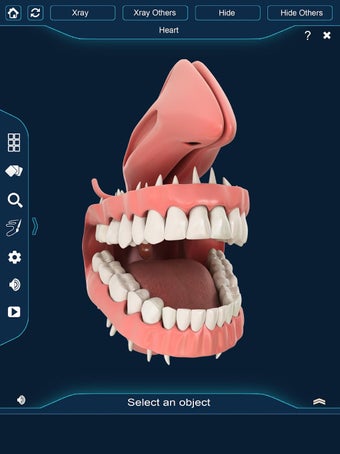

Esta aplicación es un modelo 3D de los dientes, que contiene muchas partes y muestra las condiciones dentales. Cada parte tiene un nombre y una función. Puedes mover la cámara alrededor del modelo para obtener una vista de 360° de las diferentes partes. Puedes hacer zoom para ver mejor cada parte. También puedes rotar la cámara para obtener una vista diferente del modelo.